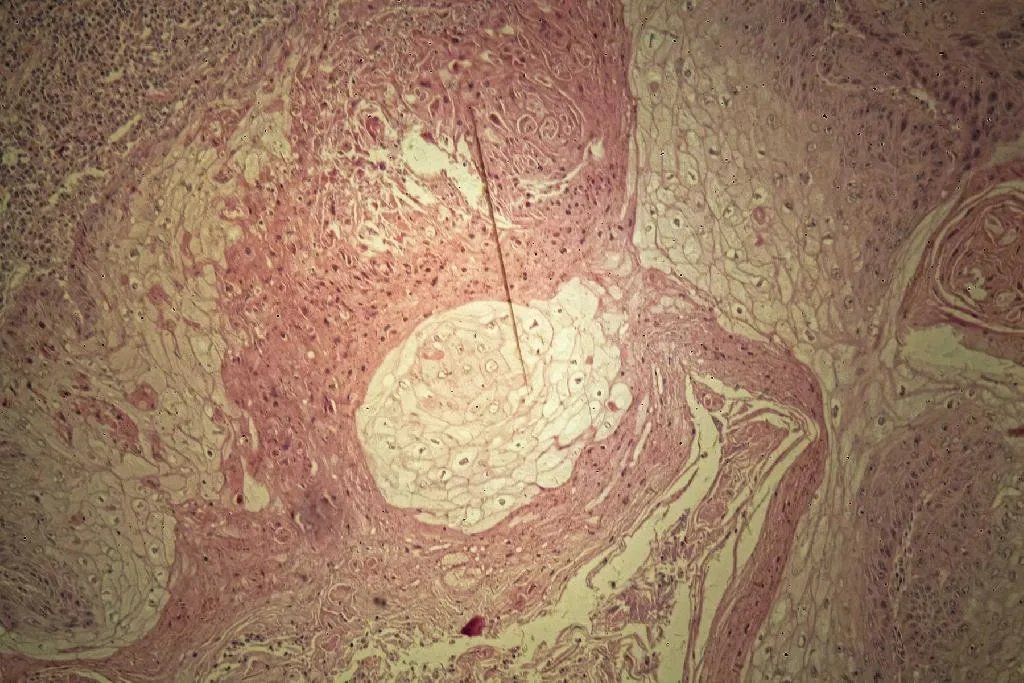

鳞状细胞癌病理图分级通过病理性检查,以肿瘤细胞分化比率、肿瘤细胞非典型性的程度,可将鳞状细胞癌分为四级:一级,病变侵入深部不超过汗腺水平,患处周围基底层部分完整,部分与周围基质分界不清。分化良好的鳞状细胞占75%以上,大多数细胞间桥发育良好,角珠数量多,真皮炎症反应明显。二级,病变处与周围基质界限不清,分化良好的鳞状细胞占50%以上,仅有少数角珠,有相当多的间变细癌细胞胞。三级,病变处与周围间质分界不清,分化良好的鳞状细胞占25%以上,许多部位角化现象消失,不见角珠,仅小片或个别细胞角化。大多数肿瘤细胞胞核呈非典型性,核分裂象多见,许多呈不典型核丝分裂。四级,病变处正常鳞状细胞少于25%,绝大多数为间变细胞,角化现象几乎完全缺乏,无细胞间桥。仔细观察才能找到细胞间桥和少数角质形成细胞而作出诊断,在分化差的鳞状细胞癌损害Vi‐mentin染色亦为阳性。治疗鳞状细胞癌的早期诊断,对于治疗效果至关重要,治疗应彻底避免转移。可根据肿瘤大小、组织分化程度、患者年龄、身体状态等多方面因素,综合评估出适当的治疗方案。目前临床应用的治疗包括Mohs显微外科、放射疗法、电干燥疗法、光动力疗法、β胡萝卜素、干扰素,以及损害内注射氟尿嘧啶等。已经转移或晚期患者,可试用顺铂、阿霉素、博莱霉素等药物治疗。